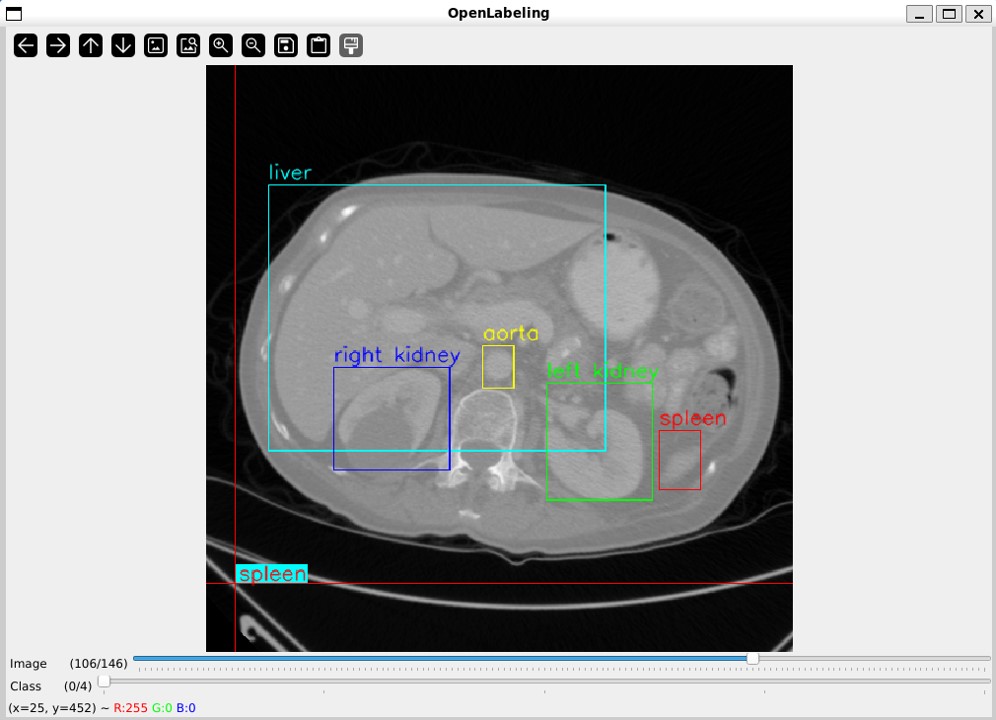

We implemented a pipeline for crowd-sourcing annotations with SAM for the purpose of training 3D DL segmentation models (Figure 2). Since the volumes are provided in the NIfTI format, we used med2image (version 2.6.6) to convert a NIfTI volume into PNG images for each slice. The PNG format was chosen as it is a lossless standard format for image analysis in computer vision. We used the OpenLabeling tool (version 1.3) to annotate the organs of interest for each slice within a volume [4]. Bounding boxes were chosen as the sparse annotation method due to their superior performance for generating segmentation masks with SAM [5, 6, 16, 15]. In this study, we evaluate the effectiveness of SAM-generated annotations for training 3D DL segmentation models across two experiments: 1) simulated ”sparse” annotations, and 2) crowd-sourced ”sparse” annotations.

Refer to caption

Figure 3: Illustration of the OpenLabeling tool used for crowd-sourcing bounding box annotations for the BTCV training set across the five organs of interest.

2.3.2 Crowd-Sourced Annotations

The goal of this experiment was to represent a real-world scenario when crowd-sourcing annotations from non-experts. We randomly split the BTCV dataset into training (n=15𝑛15n=15) and testing (n=15𝑛15n=15) sets. The training set was annotated with the five organs of interest by four non-experts from diverse backgrounds with small-to-moderate knowledge of anatomical structures (Figure 3). Two annotators (A.K., D.S.) had software engineering backgrounds, one annotator (A.C.) had a bioengineering background, and one annotator (D.C.) was a medical student. All annotators had experience in biomedical informatics with a mean 2.50 years of experience (range 1–5 years). They were provided with basic orientation to familiarize them with relevant anatomical structures. Three annotators were assigned one task (D.S., aorta; A.C., liver; A.K., spleen) and one annotator was assigned two tasks (D.C., left and right kidneys). They were instructed to draw bounding boxes surrounding the region of interest for each slice in a volume. The volumes were annotated by the non-expert annotators independently, and consensus agreement was not required.